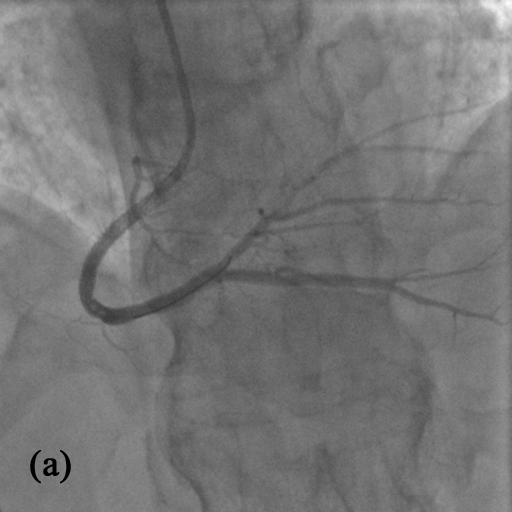

Figure 4: XCA vessel extraction results. (a) Original XCA image. (b) MoG-RPCA[37]. (c) MCR-RPCA[3]. (d) CORONA[23]. (e) VRBC[22]. (f) RPCA-UNet[17]. (g) msRPCA-PBNet. Red box regions show the small vessel detection performance and blue box regions show the interference suppression performance

4.4 Visual Evaluation of Vessel Extraction

The moving contrast-filled vessel extraction results are shown in Fig. 4, where the regions in red boxes show the small vessel extraction performance and the regions in blue boxes show the interference suppression performance. Traditional RPCA-based methods achieve good performance in major vessel extraction. The major vessel components can be clearly distinguished from the background. However, the contrast between distal vessels and the background is relatively small, and there are still many background artefacts in the final results, which further reduces the visual effect of distal vessels. Although this phenomenon has been improved in the MCR-RPCA method, such performance still has much room for improvement. The VRBC-based method has made significant improvement in the suppression of background artefacts, and the obtained extraction results contain almost no components other than target vessels. However, break points exist in the vessel extraction results, especially in the positions where the contrast between vessels and the background is low.

Compared to these methods, RPCA unrolling-based RPCA-UNet and msRPCA-PBNet significantly improve the vessel extraction performance since the extracted vessel tree structure is more complete and clear. The msRPCA-PBNet method presents more pure results with fewer background impurities compared to the previous RPCA-UNet. Moreover, the proposed method performs better in vessel detail extraction, especially for the distal vessels with low contrast. For example, in the first row of Fig. 4, red box region has quite low contrast between distal vessels and background, VRBC and RPCA-UNet can hardly extract such vessel details clearly. Traditional RPCA-based methods can extract some of them while introduce many background artefacts. However, msRPCA-PBNet can extract distal vessels exactly without introducing artefacts and noises. In blue box regions, the edges of spine structure have similar intensities and shapes to XCA vessels, RPCA-UNet and traditional RPCA-based methods extract them wrongly while msRPCA-PBNet remove the interference of such vessel-like structures. Furthermore, the regions in red and blue boxes of Fig. 4(f-2) and Fig. 4(g-2) clearly show that msRPCA-PBNet outperforms RPCA-UNet in recovering continuous heterogeneity of vessel information with simultaneously removing block and blur effects as well as residual interferences.